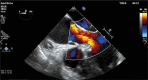

The main goal of minimally invasive surgery is to reduce the perioperative trauma, accelerate patient mobilization and reduce the length of hospital stay. Due to the development of modern technology, these treatments can be offered to a wider group of patients. For many years, aortic root surgery consisted of mechanical conduit implantation and, therefore, necessitated life-long anticoagulation. At present, in patients with aortic root aneurysm and significant aortic valve regurgitation, it is possible to perform minimal-access valve sparing surgical procedures. The current paper is a brief description of the surgical technique for aortic root aneurysm surgery with preservation of the patient's own valve using the David procedure.